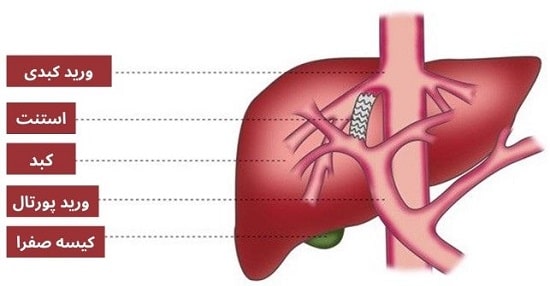

خونریزی واریس مری یک مورد اورژانسی است که نیاز به درمان فوری دارد. بیمار در بیمارستان مقدار زیادی مایعات و خون دریافت میکند تا جایگزین خون از دست رفته شود. دو درمان مختلف غیرجراحی جهت توقف خونریزی واریس وجود دارد: لیگاسیون واریس که از طریق آندوسکوپ و شنت پورتوسیمتیک داخلی کبدی داخل جفتی (TIPS) توسط متخصص رادیولوژیست با تصویربرداری اشعه ایکس انجام میشود.

شنت پورتوسیمتیک داخلی کبدی داخل جفتی (TIPS)